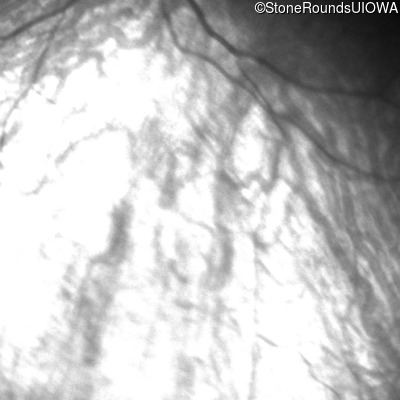

Fundus Photography - Right -

No Light Perception

Exemplar

Fundus Photography - Left -